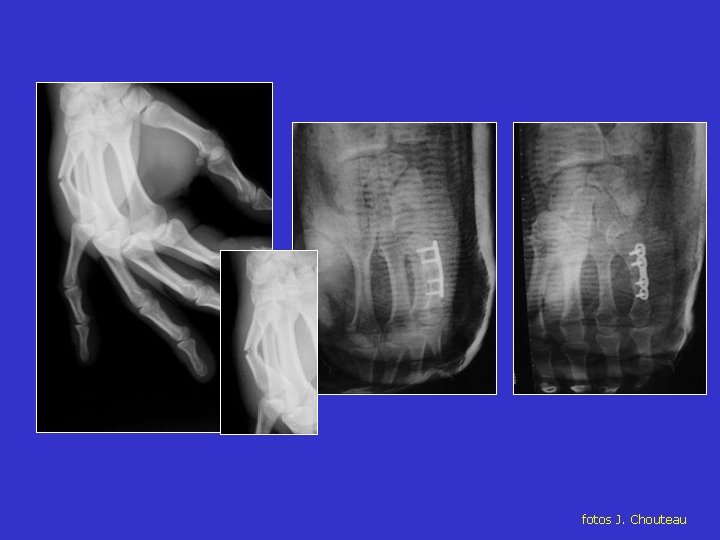

Fracturas de los Metacarpianos

Desplazamiento de la fractura del cuello del Metacarpiano

Fractura del cuello del Metacarpiano

fotos J. Chouteau

Osteosíntesis de las fracturas de los metacarpianos